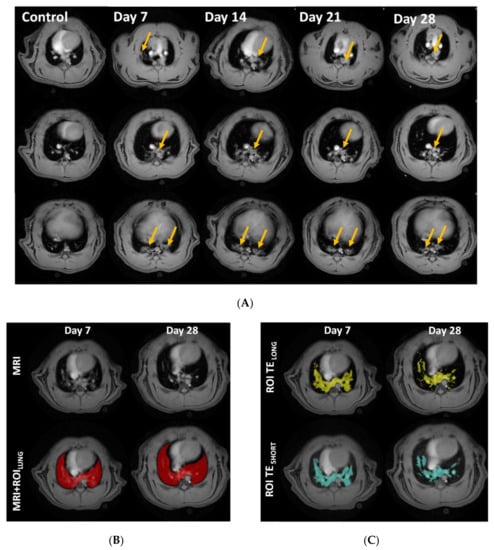

The axial MR-images of the thorax display the lungs as dark areas. The muscle tissue, heart, liver, vessels, and lesions are depicted as bright objects (Figure 3A). The lung volume originally segmented for data extraction (Figure 3B), was assessed by histogram analysis. The extracted lesion volume from the TESHORT and TELONG MR-images resulted in slightly different areas (Figure 3C). MRI measures expressed a distinct edema peak at day 7 (Figure 3D) and a tissue peak at day 28, indicating mostly acute inflammation during the first week of this model, while fibrosis appears later (Figure 3E).

Figure 3.

Longitudinal magnetic resonance imaging (MRI) in Group I, during 28 days of bleomycin-induced lung injury. (A) Representative MRI images of lungs from rats challenged by i.t. administration of bleomycin (or saline as controls), on day 7, 14, 21, and 28 post-challenge. Yellow arrows point out identified lesions (B) MRI defined Lung-ROIs and (C) UTESHORT and UTELONG defined regions in yellow and blue, respectively. Quantification of the lesion signal assessed by the two different MRI sequences was calculated for (D) “edema” signal indicating peak inflammation in bleomycin challenged rats at day 7, while (E) the calculated “tissue” signal appears to peak at day 28.